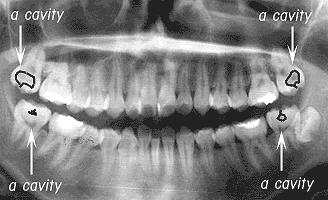

Fig. 2 CASE A

Although in the case of the second molar of the upper right the nerve was removed, the three remaining cavities were packed with resin and that ended the medical treatment.

CASE A. A woman who was 17 years old at the time of first medical examination.

She visited the dental clinic because the tooth at the back of the lower left side was causing concern. She could check the lower molar using a mirror relatively easily. However because the upper molars were difficult to check in the mirror development there was going on unnoticed. In fact a deep cavity which had reached the nerve was developing in the far most left and right of the upper teeth. Looking at the X ray the cavities development is obvious. Total medical treatment of the four cavities, including a small cavity in the lower right tooth, was performed. Since the upper right secondary molars had reached the nerve the dental pulp was removed.